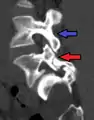

MRI of L5-S1 anterolisthesis

X-ray of a grade 4 anterolisthesis at L5-S1 with spinal misalignment indicated

Anterolisthesis L5/S1

Anterolisthesis L5/S1. Blue arrow normal pars interarticularis. Red arrow is a break in pars interarticularis.